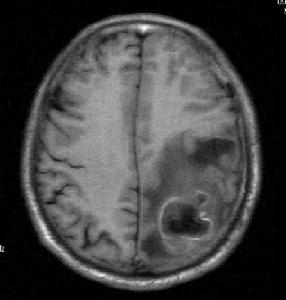

8、腦CT 是目前診斷腦膿腫的主要方法,適用於各種部位的腦膿腫。由於腦CT檢查方便、有效,可準確顯示膿腫的大小、部位和數目,故已成為診斷腦膿腫的首選和重要方法。腦膿腫的典型CT表現為:邊界清楚或不楚的低密度灶(0~15HU),靜脈注射造影劑後,膿腫周邊呈均勻環狀高密度增強(30~70HU),膿腫中央密度始終不變,膿腫附近腦組織可有低密度水腫帶,腦室系統可受壓、推移等。如膿腫接近腦室,可引起腦室管膜增強征。少數腦膿腫的增強環不均勻,或有結節狀。可是腦CT顯示的"環征"並非腦膿腫特也可見於神經膠質母細胞瘤、轉移癌,囊性膠質細胞瘤,腦梗塞和腦內血腫等。因此應結合病史注意鑑別。一般腦膿腫有感染史,CT顯示的環較均勻,伴有室管膜增強,還是容易識別。在腦炎晚期,CT也可顯示"環征",此乃因腦炎引起血腦屏障改變,血管周圍炎性細胞浸潤和新生血管形成等所致,因此腦炎的"環征"與膿腫包膜的"環征"在本質上不同。兩者的區分,除結合發病時間外,可採用延遲CT檢查法,即在靜脈注射造影劑30分鐘後掃描,腦炎原來低密度中央區也變成高密度,但膿腫中央區密度不變。由於類固醇激素有抑制炎症反應和成纖維增生、新生血管形成的作用,從而影響膿腫包膜形成,因此,對可疑病人應停用激素後重複CT檢查。

9、磁共振成像(MRI)是近年套用於臨床的新檢查方法。在腦炎期病灶呈邊緣不清的高信號改變,中心壞死區為低信號改變,T2(橫弛豫時間)延長,周邊腦水腫也呈高信號變化,灰白質對比度消失,T1(縱弛豫時間)和T2也延長。腦炎晚期的病灶中央低信號區擴大,IR(反向復原)成像示中央區仍為低強度。包膜形成期的中央區低信號,T1延長,但在長TR(重複時間)成象時原低信號變成較腦脊液高的高信號。包膜則為邊界清楚的高信號環。鄰近腦灰白質對比度恢復正常,但T1,T2仍輕度延長。因此MRI顯示早期腦壞死和水腫比CT敏感,區分膿液與水腫能力比CT強,但在確定包膜形成,區分炎症與水腫不及CT敏感。